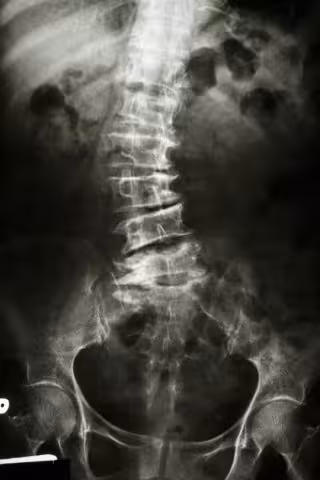

Escoliosis: la curvatura indeseada

Escoliosis, radiografia, espalada

La columna, al ser observada de frente, tiene que verse recta pero cuando se padece escoliosis aparecen curvaturas, como torceduras en la columna vertebral que provocan dolor y deformidad estética importante.

"En el diagnóstico es importante no realizar radiografías si no hay una sospecha fundada y no exponer de forma indiscriminada a los niños a la radiación que se deriva de estas pruebas que abarcan todo el cuerpo. La prueba inicial es el test de Adams, en el que el menor se dobla hacia delante y se observa si una parte de la columna sale hacia arriba, esto identifica en un inicio a quienes necesitarían pasar por una radiografía", apunta Burgos.